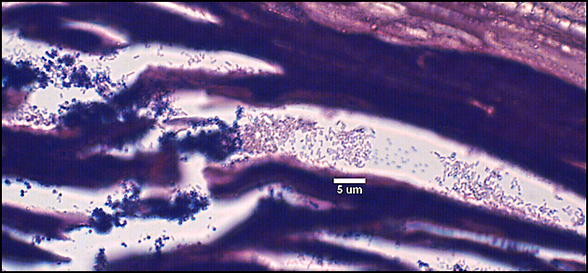

The predominant type of biofilm bacteria observed using light microscopy were Gram positive cocci (Figure 7-4). These results were in agreement with culture data which showed a predominance of Staphylococcus and Enterococcus from these patients. SEM examination of the samples confirmed the predominance of coccoid cells, which often appeared to be coated with EPS (Figure 7-5). Similar coatings were observed in pure culture biofilms of Staphylococcus aureus grown using the colony biofilm model (Figure 7-6).

Biofilms composed of Gram-negative rods (Figure 7-7) and mixed-species biofilms (Figure 7-8) were also observed. These results were confirmed by results of culture and molecular analysis, discussed below, indicating that wound biofilms are indeed polymicrobial.